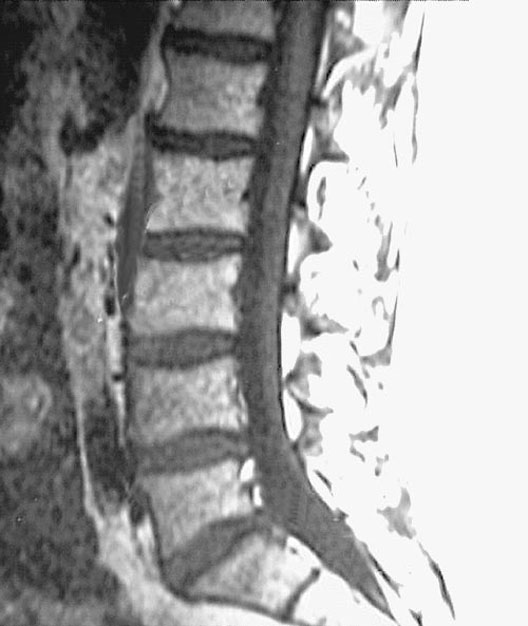

Lumbar Spine MRI

1. Spinal cord

2. Body of 2nd lumbar vertebra

3. Intervertebral disc

4. Body of 3rd lumbar vertebra

5. Lumbar cistern

6. First sacral vertebra